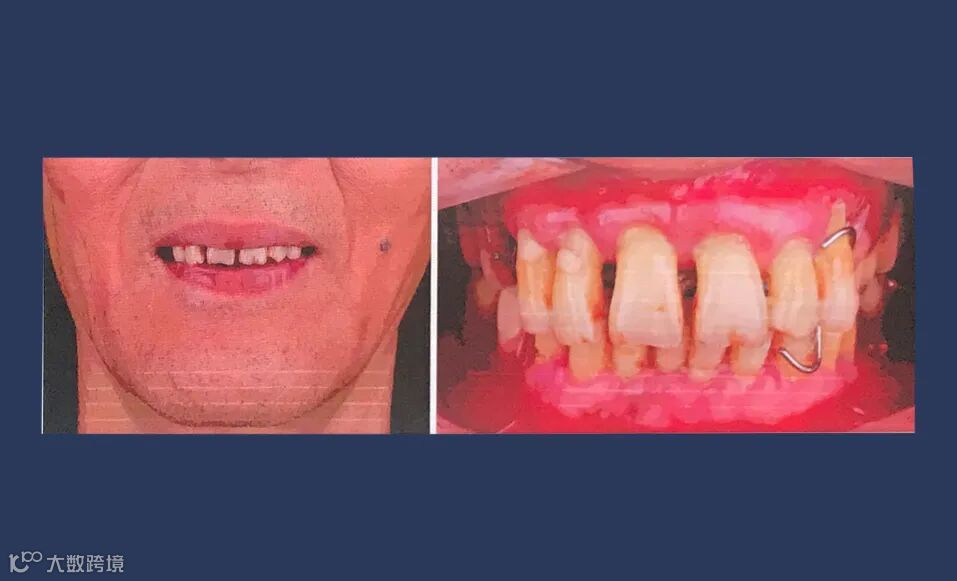

口外检查:面部对称无偏斜,面下1/3垂直高度正常,口角无偏斜,鼻唇沟加深,中线略偏右侧。低位笑线,前牙开唇露齿。开口度正常。

口内检查:13-23牙龈退缩,牙齿松动2-3度,14-17,24-27缺失,牙龈颜色质地正常,36、37、45、46、47缺失,下颌余留牙松动1-2度。

咬合检查:前牙深覆盖深覆he,后牙活动义齿咬合稳定。